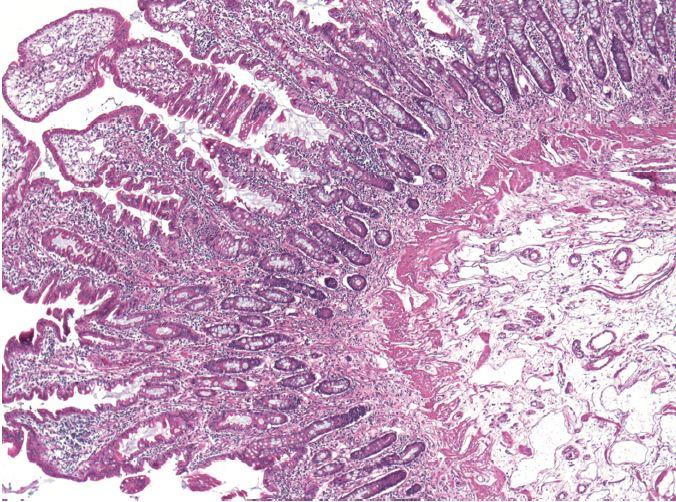

In the study, researchers from the National Institute of Allergy and Infectious Diseases (NIAID), part of NIH, describe a newly understood mechanism for CHAPLE disease, or CD55 deficiency with hyperactivation of complement, angiopathic thrombosis, and protein-losing enteropathy. The research report was published online today in the New England Journal of Medicine . CHAPLE disease is a form of primary intestinal lymphangiectasia (PIL), or Waldmann's disease, first described in 1961 by Thomas A. Waldmann, M.D., an NIH Distinguished Investigator at the National Cancer Institute, at NIH.

Researchers analyzed genes from 11 children with CHAPLE disease and their families. They found that each child had two copies of a defective CD55 gene that prevented them from producing a cell surface protein of the same name. The CD55 protein helps regulate the immune system by blocking the activity of complement, a group of immune system proteins that can fight infections by punching holes in the cell membranes of bacteria and other infectious agents. However, complement also can damage the body's tissues. The study authors found that in CHAPLE disease, uninhibited complement resulting from a lack of CD55 protein damaged blood and lymph vessels along the lower digestive tract, leading to the loss of protective immune proteins and blood cells. In many patients, this process caused a range of symptoms, such as abdominal pain, bloody diarrhea, vomiting, problems absorbing nutrients, slow growth, swelling in the legs, recurrent lung infections, and blood clots.